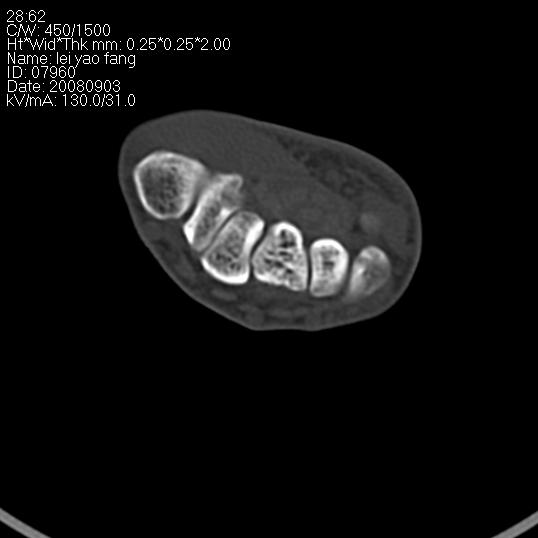

以下是引用杀毒软件在2008-9-4 17:41:00的发言:[br]考虑----舟骨囊肿